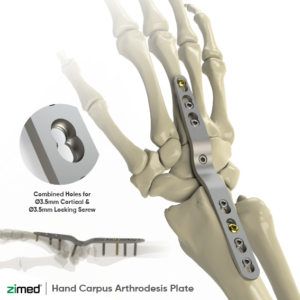

Hand Carpus (Arthrodesis) Plate